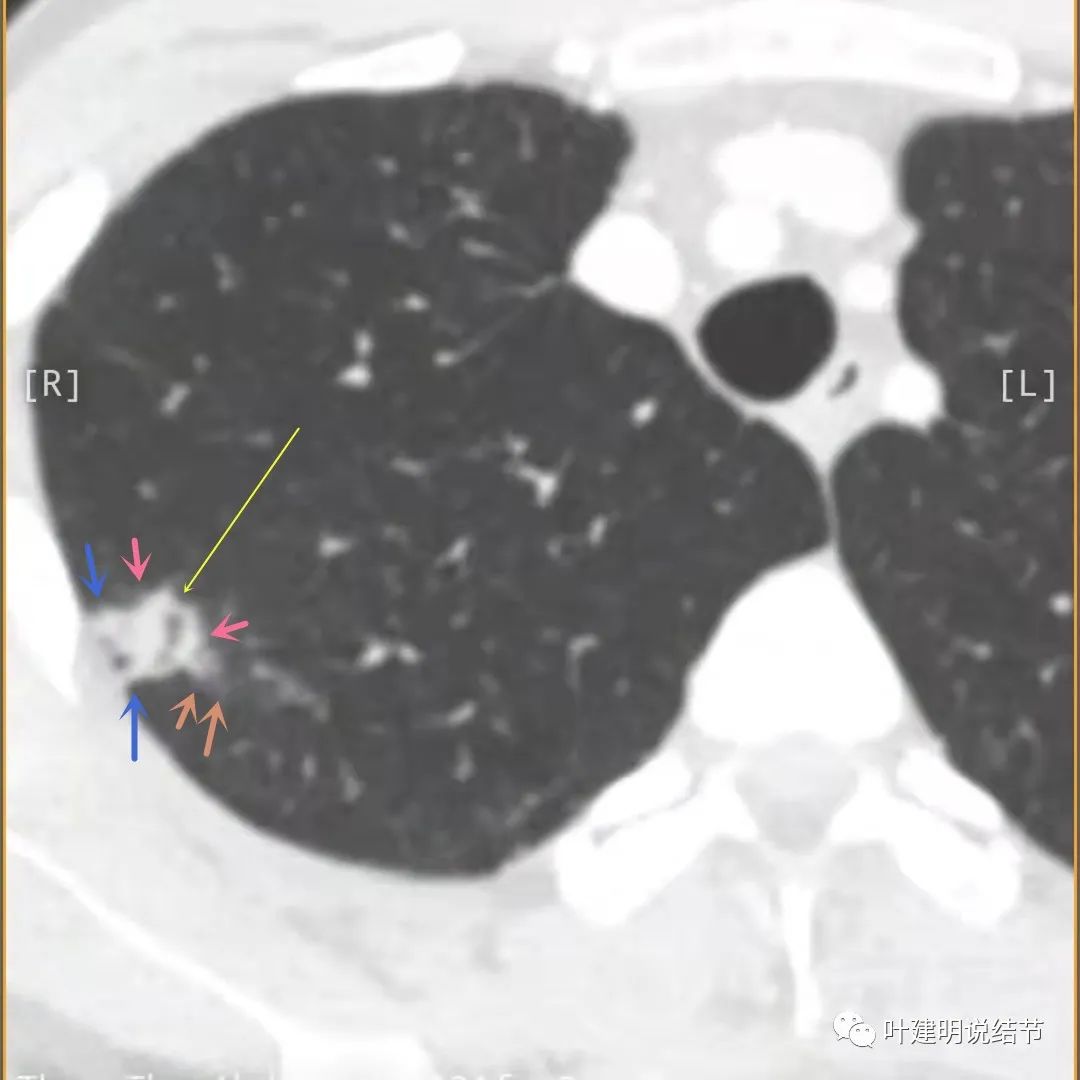

主病灶此层面似三角形,邻近胸膜增厚(蓝色箭头),结节实性部分密度较高(粉色箭头),边缘显模糊(砖色箭头)

上图与恶性较为符合,空洞性病灶,壁厚薄不均,增厚部分还凹凸不平(细红色箭头所指)

上图磨玻璃部分密度过低,且与正常肺组织界限模糊(砖色箭头),粉色箭头示囊壁密度过高的点状,蓝色箭头示邻近胸膜处的增厚

再看影像印象:病灶较1年前有所进展,部分层面像恶性,囊壁厚薄不均,内面有小突起。但邻近胸膜增厚,旁边的磨玻璃部分散且淡,边界不清,实性部分边相对较光,囊壁有点状过高密度。良性可能性大些,恶性不能除外。